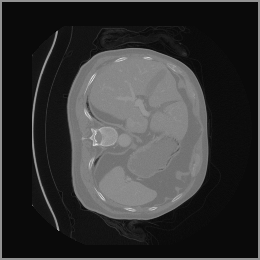

In our approach, we employ a compression factor of 4 to encode 3D medical images into the latent space. This level of compression reduces the spatial resolution of the original image (e.g., from 256×256 to 64×64 per slice), while still preserving the essential anatomical structures and semantic content. The latent representation at this scale offers a favorable trade-off between dimensionality reduction and semantic fidelity. Specifically, although fine-grained textures are simplified, key structural patterns (e.g., organ boundaries, lesion shapes) remain visually distinguishable and semantically coherent. As the compression rate increases, the latent representations become progressively more abstract. With lower compression (e.g., 2× or 4×), the latent features preserve key anatomical structures and spatial layouts, making them beneficial for our semantic image synthesis task in latent space, as the model can operate on compressed representations that retain sufficient semantic information without being overwhelmed by high-frequency noise. In contrast, higher compression rates (e.g., 8× or above) lead to a loss of fine-grained details and reduced semantic fidelity. The choice of a 4× compression thus ensures that the latent features are compact and meaningful, facilitating effective conditional generation while significantly reducing computational overhead. We therefore adopt a 4× compression as a compromise between computational efficiency and semantic preservation. The corresponding 2D slices in image space and latent space are shown in Figure 7.